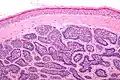

Dermal cylindromas are:

- Dermal lesions consisting of nests of cells that are surrounded by hyaline (i.e., glassy, eosinophilic, acellular) material and have:

- Hyperchromatic nuclei that may palisade (columnar nuclei arranged around the periphery of the cell nests with their short axis tangential to the nest periphery), and

- Cells with lighter staining ovoid nuclei at their centre.

They lack of a significant number of lymphocytes; this differentiates them from spiradenomas.